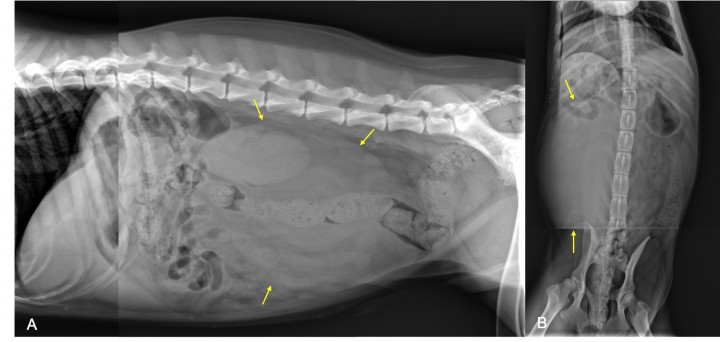

Se evidencia una lesión retroperitoneal de opacidad tejido blando, ovoide, de gran tamaño (25 cm aproximadamente) que provoca un efecto masa y desplazamiento del paquete intestinal craneoventralmente y a la izquierda. Existe buen detalle de la serosa y no se evidencian alteraciones en las estructuras óseas o tejido blando periférico (Fig. 2).

<p>Mismas radiografías de la Figura 1. Se observa una lesión retroperitoneal de opacidad tejido blando (flechas amarillas) que provoca efecto masa y desplazamiento del paquete intestinal craneoventralmente y a la izquierda.</p>

Mismas radiografías de la Figura 1. Se observa una lesión retroperitoneal de opacidad tejido blando (flechas amarillas) que provoca efecto masa y desplazamiento del paquete intestinal craneoventralmente y a la izquierda.

Los hallazgos radiográficos sugieren una masa renal derecha (hidronefrosis grave, quiste perinéfrico, neoplasia o absceso renal) o tumor retroperitoneal primario.